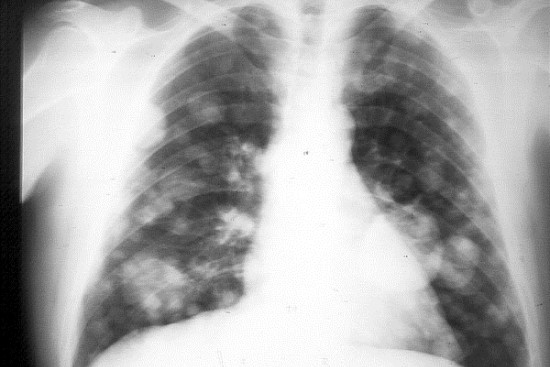

Científicos mexicanos de la Universidad Nacional Autónoma de México (UNAM) desarrollan pruebas en sangre que ayuden a determinar la respuesta que un paciente con cáncer de pulmón va a tener ante su tratamiento, informó este viernes la institución en un comunicado.

Con la finalidad de contar con métodos menos invasivos y más económicos que otros, como las biopsias, un grupo de científicos trabaja para localizar, en sangre, las células inmunosupresoras que provocan que el sistema inmune de los pacientes deje de reconocer al tumor como algo que debe ser atacado y removido.

Los también integrantes de la Unidad Funcional de Oncología Torácica del Instituto Nacional de Cancerología (INCan) aseguraron que este tipo de pruebas en sangre podrían hacerse de manera rutinaria en los pacientes con cáncer de pulmón y otras neoplasias como cáncer de ovario, gástrico y de colon.